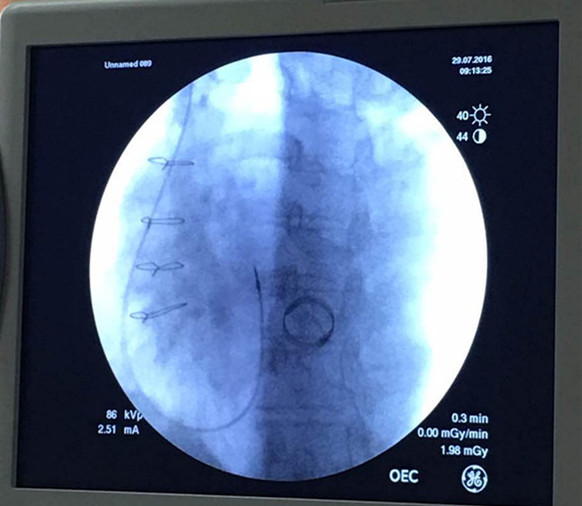

济宁市第一人民医院心内科孙晓斐教授成功的为1例巨大右心房患者植入心脏起搏器,属全国亦罕见。该患者为房颤合并三度房室传导阻滞,平均心率40次/分左右,但患者右心房巨大,心脏超声提示右心房大小46*96mm,右心室前后径22mm,心脏起搏器植入术需将起搏电极送至右心室,但因此类患者右心房巨大电极容易漂浮在右房,很难到达心室,即使电极到达心室因巨大右房的牵拉很容易弹出,导致电极脱位,在手术过程中,同样出现了电极难以到位(图1 电极在右房),到位后电极被弹出及电极脱位,但最终孙晓斐教授凭借30余年上千例心脏起搏器植入手术的经验,成功为患者完成手术(图2 电极在室间隔下部),解除病痛,康复出院。